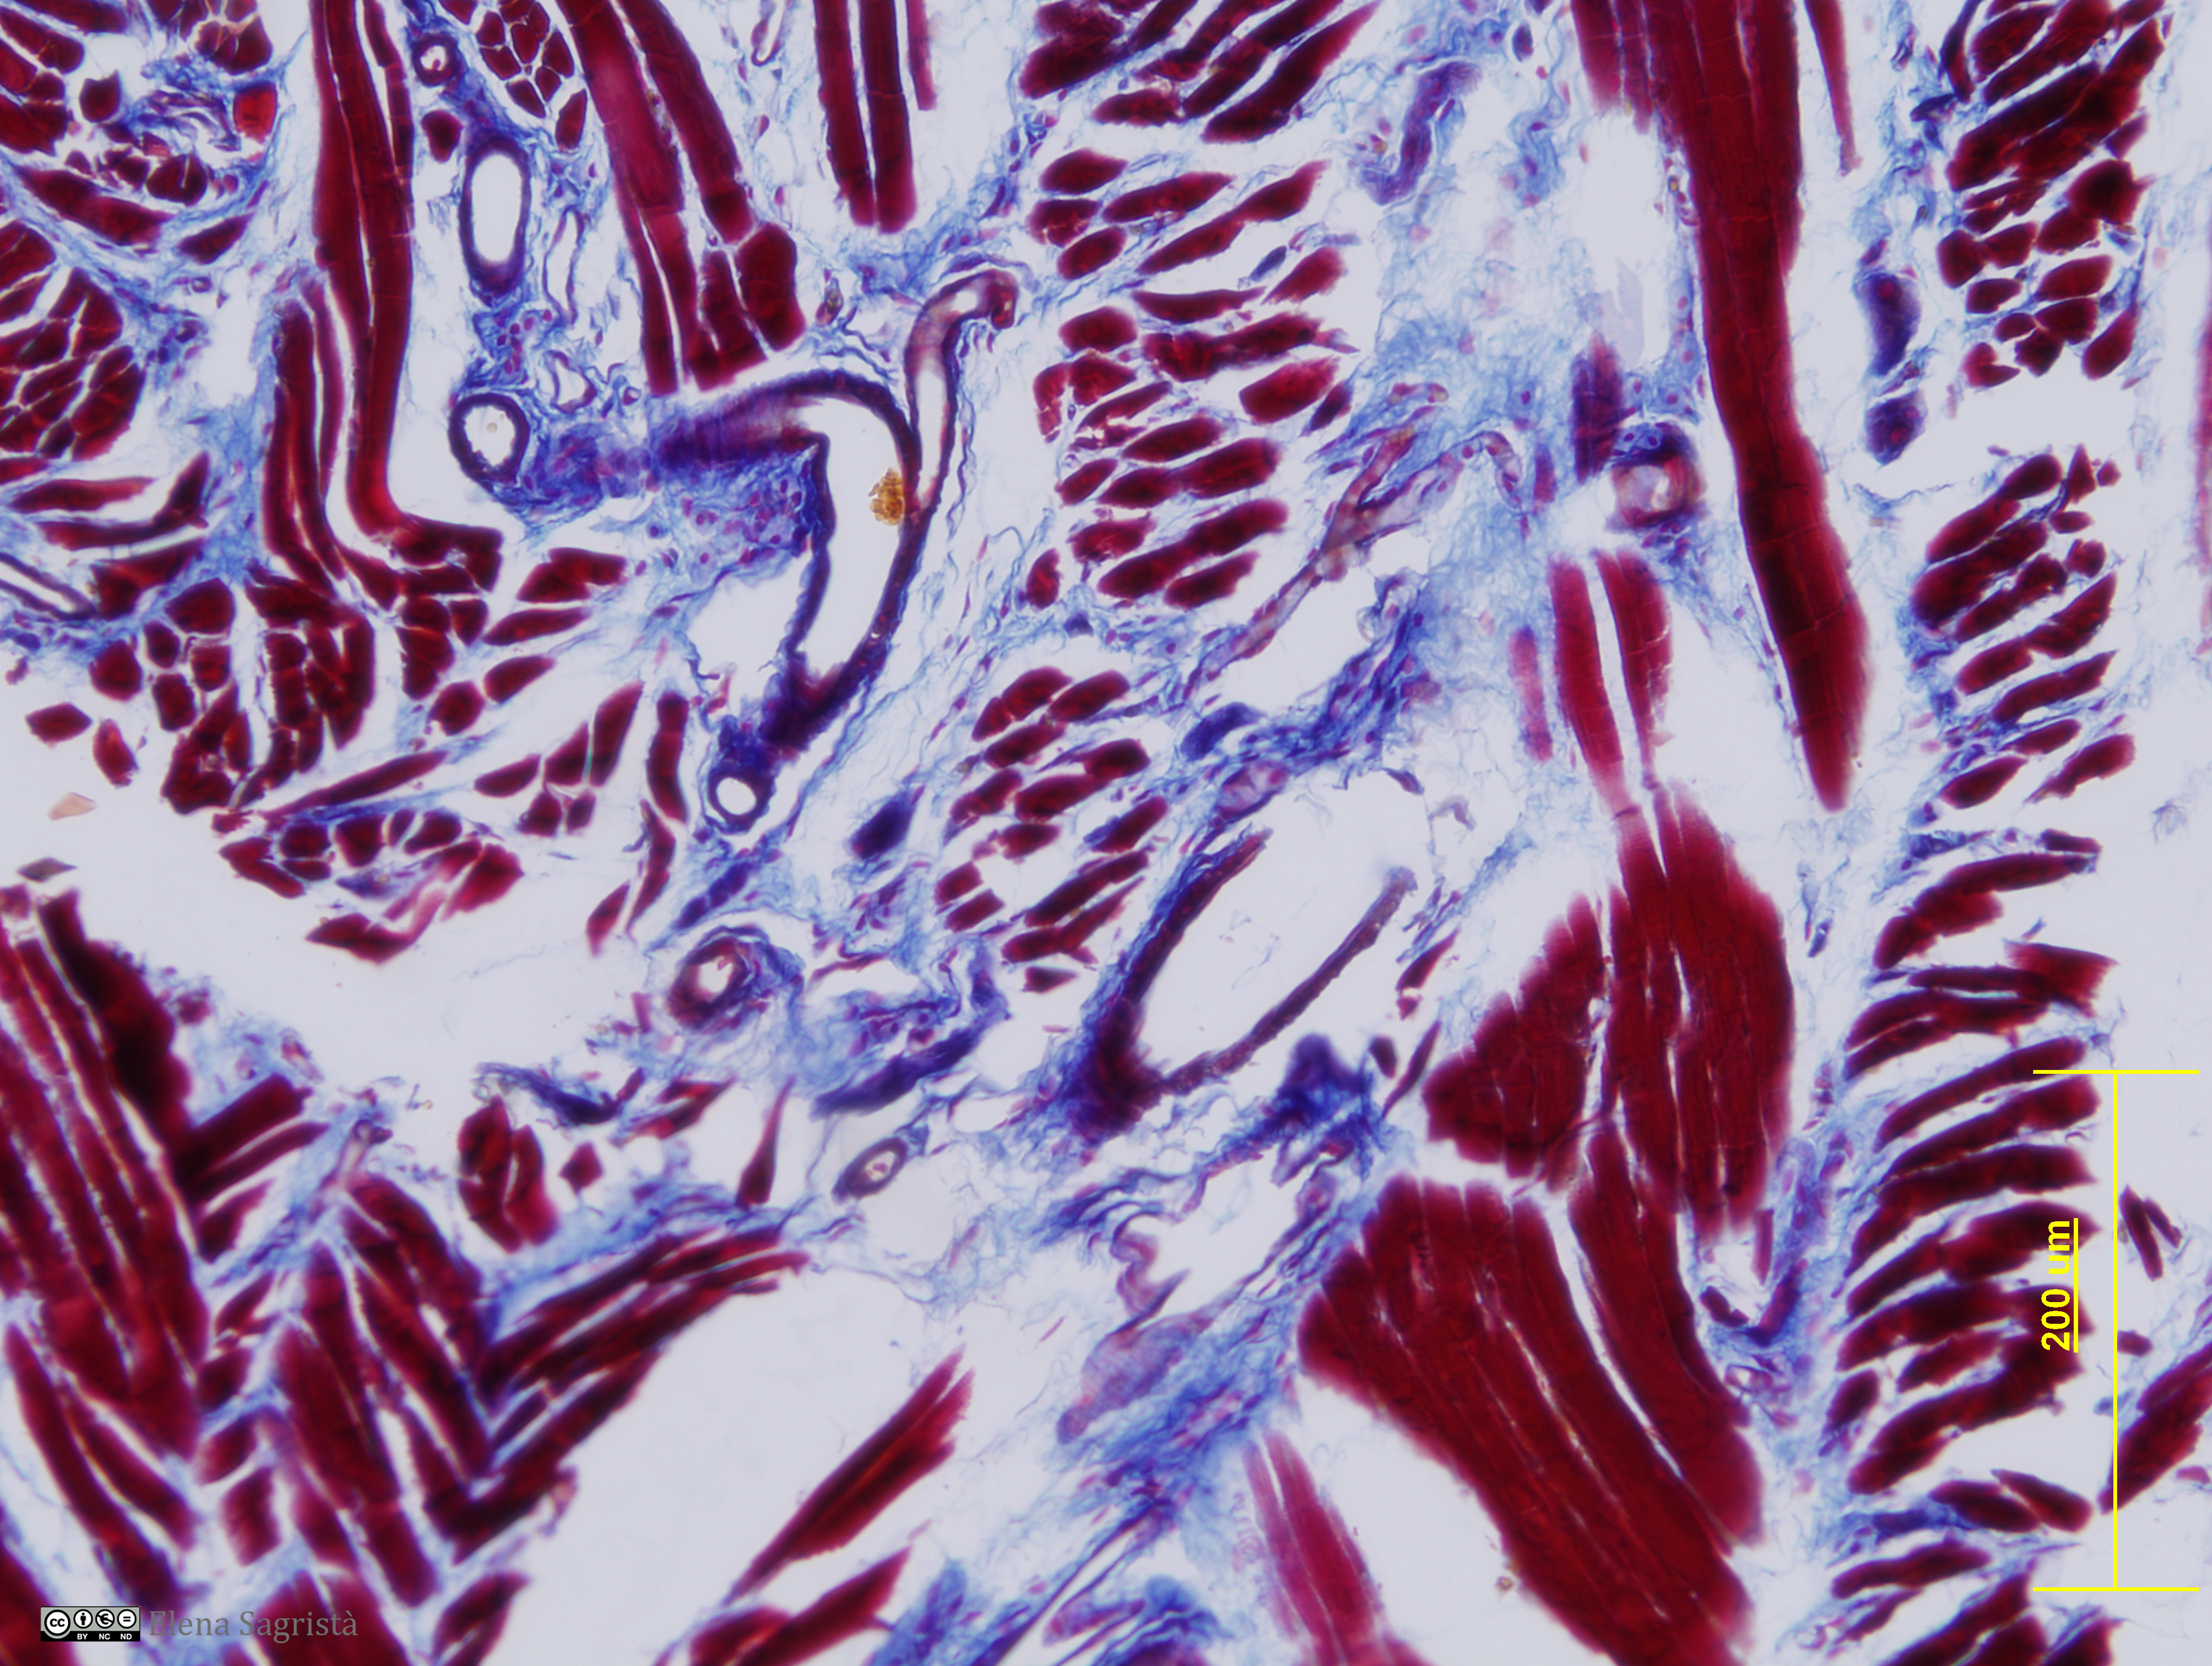

Histologia imatges: 07 Teixit muscular

Imatges de preparacions histològiques de Teixit muscular. Microscopia òptica.